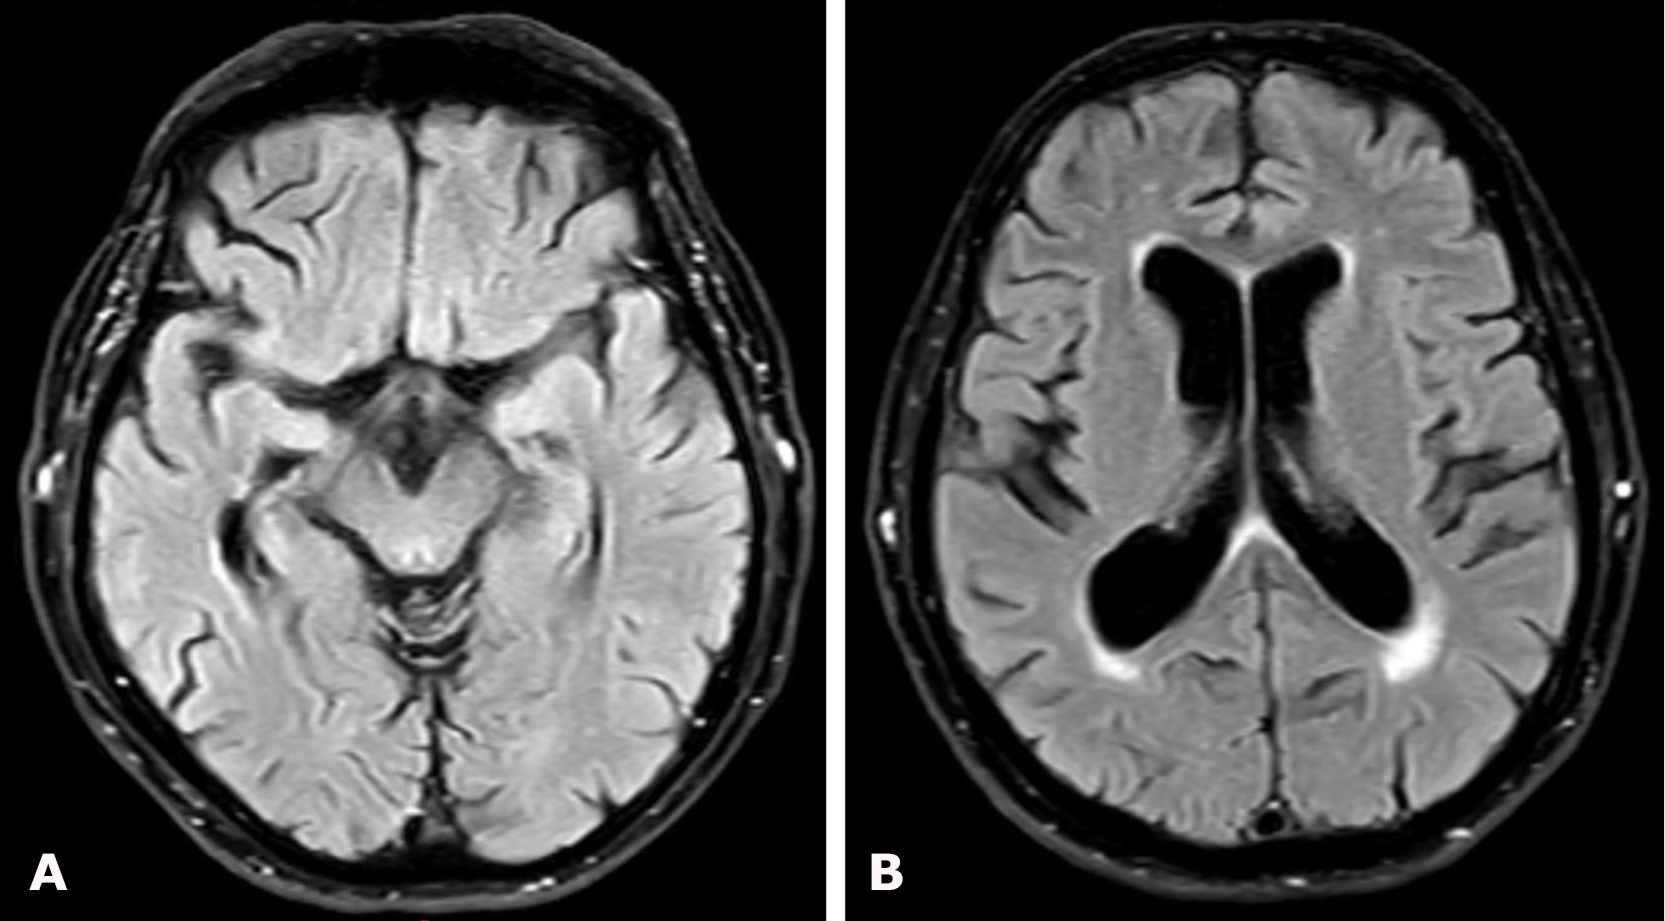

Brain MRI revealed a right-sided hemispheric chronic cSDH with dimensions (thickness/length/height) of 10/166/124 mm and a 4-mm midline shift to the left (Fig. 5).

Fig. 5. Preoperative brain MRI, T2-weighted images: A, B – axial projections demonstrating a right-sided hemispheric cSDH

Follow-up brain MRI was performed 3 months after surgery (Fig. 9). Complete resolution of the chronic subdural hematoma was observed, with restoration of the normal position of the midline brain structures. On T2-weighted images, a focus of ischemic stroke was visualized in the right frontal lobe within the vascular territory of the excluded branch of the right middle cerebral artery together with the aneurysm. At follow-up examination, no focal neurological deficits were present, and headache and dizziness had resolved.

Fig. 9. Postoperative (3-months) brain MRI, T2-weighted images: A, B – axial projections. The red circle indicates a focus of ischemic stroke in the right frontal lobe measuring 19 × 13 mm

Brain MRI demonstrated a right-sided hemispheric multiloculated cSDH with dimensions (thickness/length/height) of 27/165/87 mm and a 5-mm midline shift to the left (Fig. 10).

Fig. 10. Preoperative brain MRI, T2 FLAIR sequence: A, B – axial projections demonstrating a right-sided hemispheric multiloculated cSDH

Follow-up brain MRI performed 6 months after surgery (Fig. 12) demonstrated complete resolution of the chronic subdural hematoma with restoration of the normal position of the midline brain structures. At follow-up examination, regression of global cerebral symptoms was noted.

Fig. 12. Postoperative brain MRI, T2 FLAIR sequence: A, B – axial projections demonstrating the absence of right-sided chronic subdural hematoma (cSDH)